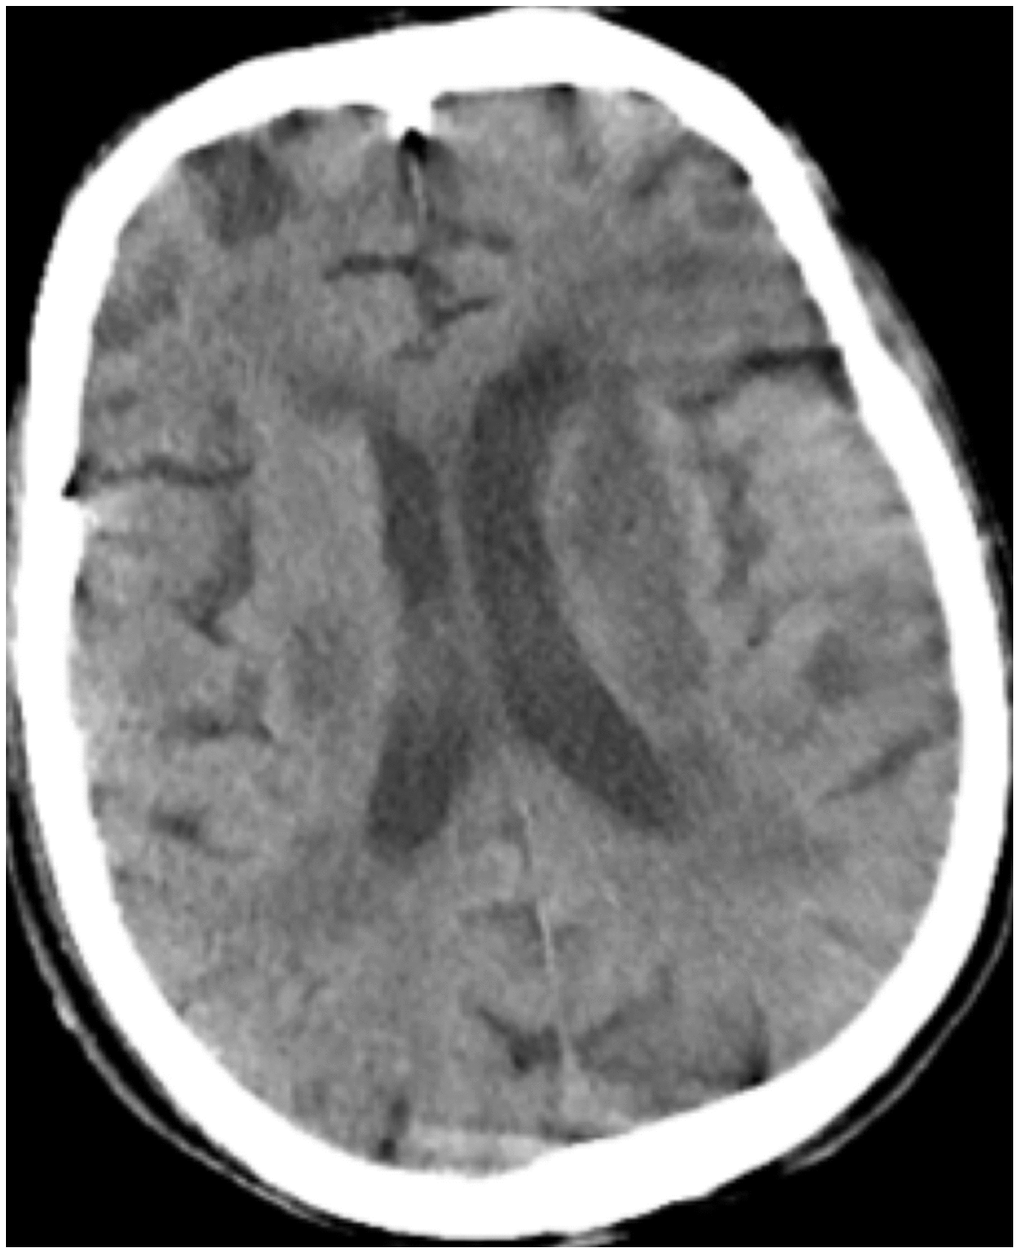

All patients were positive for the coronavirus nucleic acid test from pharyngeal swabs or blood. The blood lymphocyte counts and proportions of all patients were lower than normal (0.8×109/L) at the time of admission, and the white blood cell counts and proportions of six patients were higher than normal value (10×109/L). The blood D-dimer levels in all patients were higher than normal value (243 ng/mL) before neurological symptoms, and the C-reactive protein values in all patients were also higher than normal value (8000 μg/L). The chest CT of all patients showed flaky or frosted glass like- high-density shadow in lungs (Figures 1, 2), pleural effusion was seen in 2 cases (Figure 3), and no obvious abnormalities in 4 cases. The head CT imaging indicated that one patient had brainstem hemorrhage with ventricular cast and hydrocephalus (Figure 4), two patients had a large area of uniform low-density shadow on the frontotemporal lobe on the head CT (Figure 5), four patients had multiple flaky low-density shadow on the parietal lobe (Figure 6), one patient showed flaky low-density shadow in the pons (Figure 7), and three patients could see point-like low density shadow in basal ganglia (Figure 8).

Figure 4. Case 3, head CT imaging: one patient had brainstem hemorrhage with ventricular cast and hydrocephalus.

Figure 5. Case 2, a large area of uniform low-density shadow on the left frontotemporal lobe.